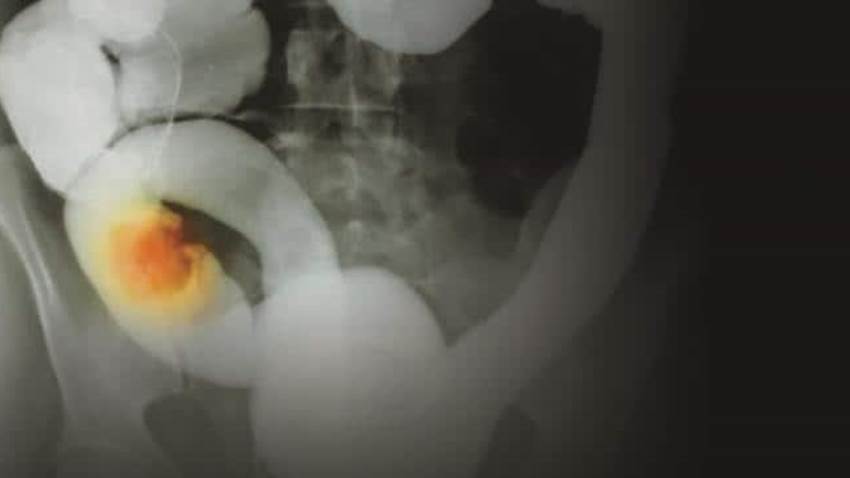

Continúan avanzando los tratamientos contra el cáncer de colon en Puerto Rico

El cáncer de colon en Puerto Rico ha mejorado en el diagnóstico y la prognosis siendo un cáncer retante hace 2 o 3 décadas.  Hoy día  gracias a los tr...

El cáncer colorrectal es una enfermedad más común en hombres y aumenta el riesgo a partir de los 50 años

El cáncer colorrectal puede surgir debido al desarrollo de pólipos que se convierten en adenomas y estos continúan su transformación neoplástica hasta...